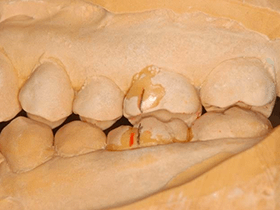

ある矯正治療後の患者様の治療例です。

矯正治療が終わって2年ほど経過してから、口を開けると顎がガクガクなるそうです。

耳の近くに少し痛みもあるようでした。

歯並びも美しく、矯正治療に問題があるようには見えません。

しかし、咬み合わせの分析を行うと、生理的な咬み合わせに歪みが生じていました。

歯がすり減ってしまい奥歯の裏側に隙間があります。 これでは咬んだ時に顎が横にずれてしまい、しっかりと咬めません。

追加する部位をまずプラスチックで作製し、お口の中に歯を削らずに装着してテストします。

そのまま、しばらく日常生活を送っていただき、咬み合わせや顎の関節の状態が改善することを確認します。

経過に問題がなければ、最終修復としてセラミックスを貼り付けて仕上げます。

セラミックスは擦り減らない上に生体親和性も高いため、当院では推奨しております。

患者様には『すごく咬みやすく、顎も楽になりました!』と喜んでいただけました。